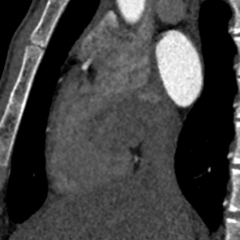

冠状动脉CTA:冠状动脉分布呈均衡型,左前降支中段浅肌桥;余冠状动脉CTA未见明显异常;卵圆孔未闭;左房囊袋。

冠脉CTA(长隧道+大开口+左房囊袋PFO)

冠脉CTA进一步提示PFO呈“长隧道+大开口+左房囊袋(LASP)”特征;经胸右心声学造影显示静息状态下中量右向左分流,瓦氏动作后为大量右向左分流。依据PASCAL分类系统评估,RoPE评分9分且合并PFO高危解剖学特征4分,提示症状与PFO相关性较高并具备介入获益的病理生理基础。